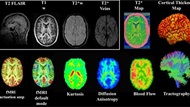

Traumatic Brain Injury Center of Excellence

TBICoE supports the MHS and DHA with traumatic brain injury research initiatives, including gap-driven analyses and congressionally directed programs such as the 15-year longitudinal study of TBI and an investigation into the effects of blast exposure on Warfighter Brain Health and Performance.